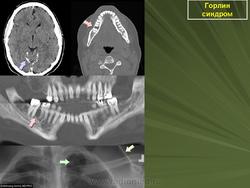

Гольца (Гольтца) (Goltz) - Горлина (Gorlin) синдром.

Наследственная болезнь, проявляющаяся образованием резко отграниченных очагов истонченной гиперпигментированной кожи, дистрофией ногтей, гипотрихозом (слабо развитым оволосенением), аномалиями развития глаз, гортани, сердца, скелета.

Рентгенологическая картина

Аномалии развития скелета (полидактилия, синдактилия, гиподактилия; микроцефалия или брахицефалия). Врожденные пороки сердца.

Горлина - Гольца синдром